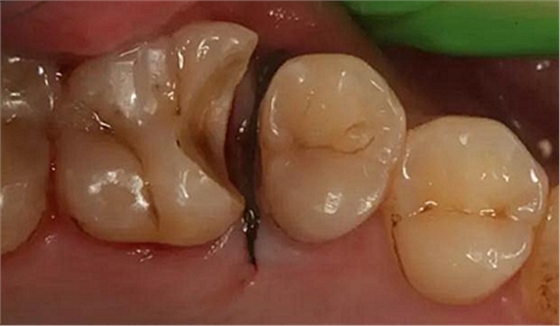

病例一 女性,20歲,大學(xué)生,要求補(bǔ)牙,檢查口內(nèi)可見A6大面積缺損,近中牙齦息肉,拍X片,根管充填物略差,但根周未見明顯陰影,口內(nèi)檢查無叩痛。建議患者冠延長手術(shù)+高嵌體修復(fù)。

患牙遠(yuǎn)中邊緣嵴完整,強(qiáng)度沒有降低,故擬保留遠(yuǎn)中邊緣嵴,高嵌體修復(fù)。首先去除腐質(zhì)及原墊底材料,流體樹脂+3M Z350XT樹脂墊底。局麻下行冠延長手術(shù)。在此需要提及個人的一個觀點(diǎn)。冠延長手術(shù)原則上要求3-6個月以上才能永久修復(fù)。但是個人喜歡后牙肩臺建立在齦上,所以修復(fù)后的修復(fù)體邊緣位于牙齦上方1mm,對牙周的愈合影響較小(如果為齦下邊緣則要慎重),故該患者術(shù)中按照齦上邊緣的設(shè)計(jì)進(jìn)行冠延長手術(shù)。以下為術(shù)中:

改良垂直褥式縫合關(guān)閉傷口,傷口無明顯滲血,高嵌體預(yù)備完畢后,硅橡膠取模,見邊緣清晰。灌注模型,模型上3MZ350XT分層堆塑高嵌體。

一周后拆除縫線,試戴高嵌體,試戴合適后雙固化粘結(jié)。調(diào)合,拋光。